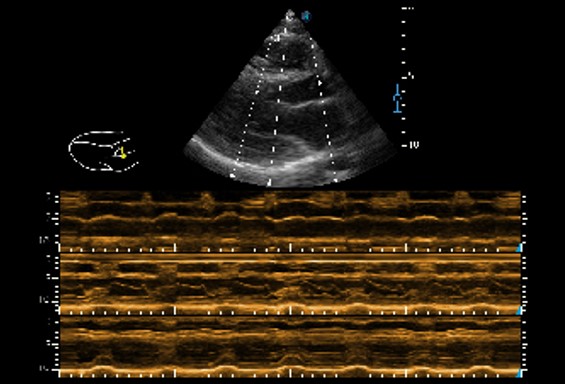

Chế độ Anatomic M

Anatomic M Mode giúp bạn quan sát chuyển động của cơ tim ở các giai đoạn khác nhau bằng cách đặt các đường mẫu một cách tự do. Nó đo chính xác độ dày cơ tim và kích thước tim của ngay cả những bệnh nhân khó khăn, đồng thời hỗ trợ chức năng cơ tim và đánh giá chuyển động thành LV.